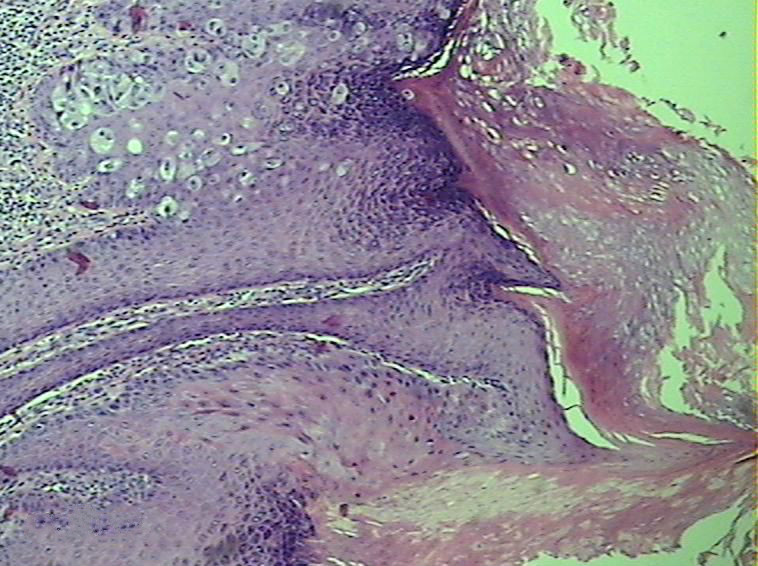

按发病部位可分为乳房Paget 病和乳房外Paget 病。阴囊Paget 病属于乳房外Paget 病,具有病程长、易侵袭、易复发和转移的特点,因其临床表现类似湿疹,且较为罕见,目前在文献中也仅报道过数百例,故而很多临床医生缺乏对该病的诊断意识,也容易导致误诊和漏诊。

但是阴囊Paget 病与阴囊湿疹还是有区别的:阴囊Paget 病以40-80岁的男性多见,少数患者有化学及放射物品接触史,属于皮肤恶性肿瘤,且病程缓慢,可能有几年到几十年的病史。临床表现为阴囊红疹、红斑、渗出性皮炎、瘙痒或烧灼样疼痛等症状;而阴囊湿疹好发于青壮年,属于慢性局限湿疹皮肤病,临床表现为局部奇痒难耐,常因搔抓或自行涂药,导致红肿、渗出、感染等。但临床对于阴囊Paget 病的确诊还是要靠病理活检。